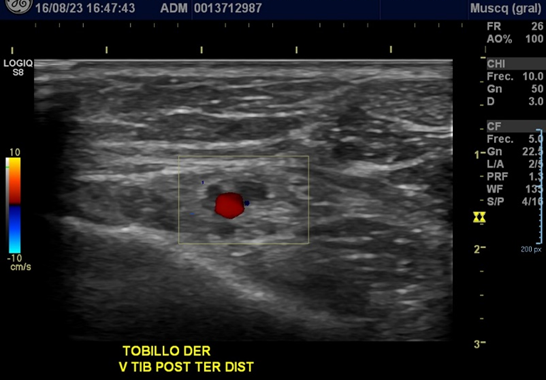

Paciente de sexo femenino de 24 años acude por dolor en cara medial del tobillo derecho, asociado a edema. Sin traumatismo. Indicación médica: Edema del tobillo.

• En cara medial de tobillo, área de dolor, se observa V tibial posterior con contenido ecogenico, no compresible, sin signos de recanalizacion vascular que se extiende hacia perforante en tobillo med y varices superficiales.

• Abundante edema en cara medial, con señal al Doppler power

Hallazgos: Trombosis venosa de venas tibiales posteriores a nivel del tobillo asociado a tromboflebitis.